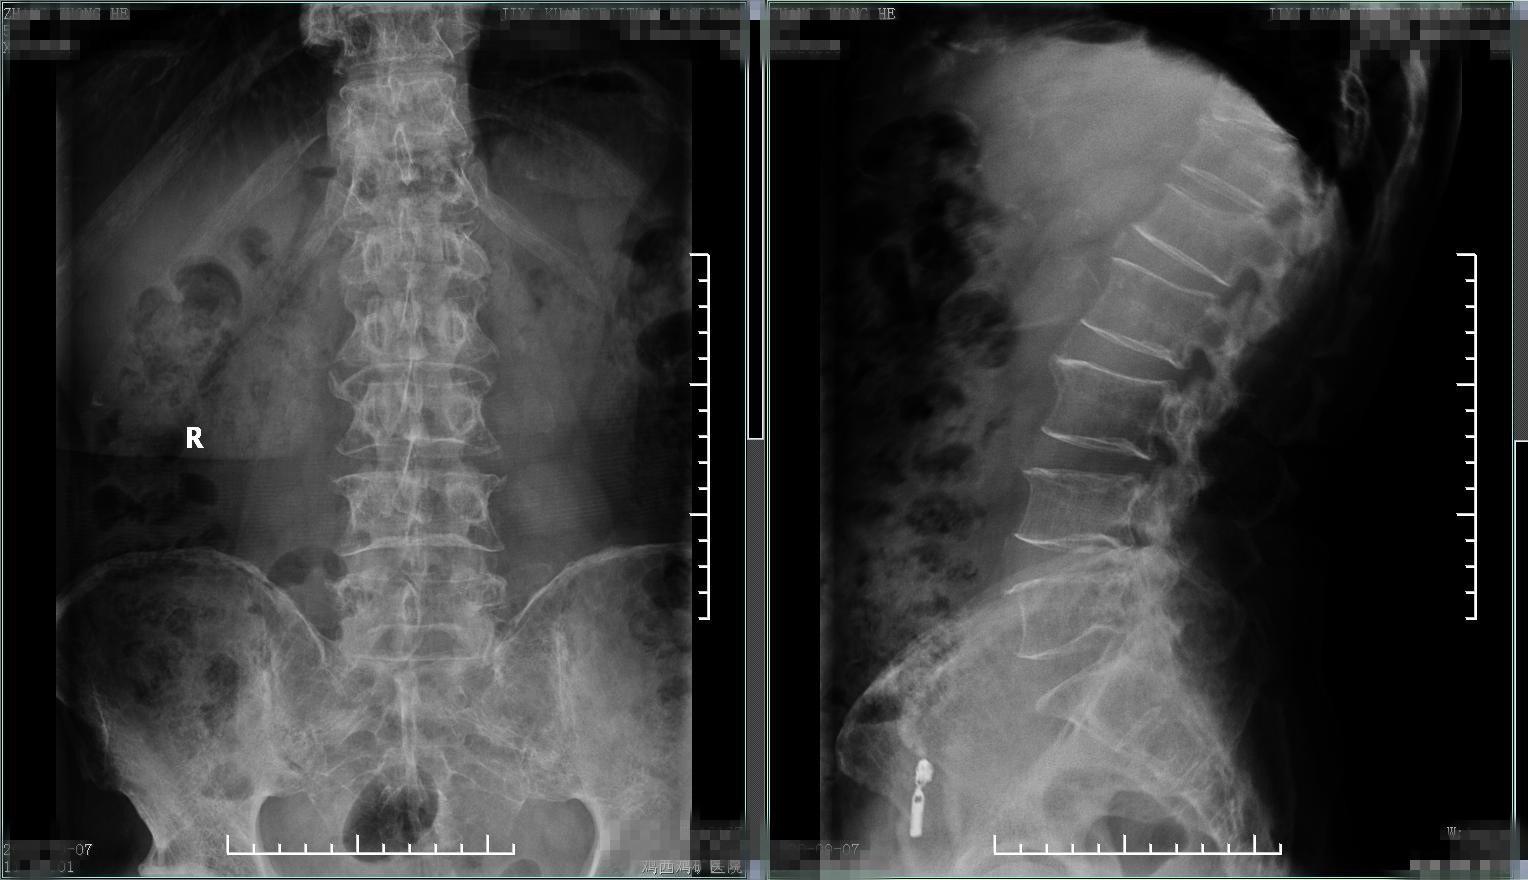

患者1、男性、57岁,病人就诊前2个月逐渐出现腰背部疼痛进行性加重,无外伤史,自行外贴膏药、口服活血化瘀药物、热敷治疗,起初症状略减轻,但1个月后逐渐出现疼痛加剧,变换体位及活动均明显收到影响,夜间常自感低热,半夜常被疼醒。查腰椎X线片,发现腰1、胸12椎体轻度变扁,骨质疏松,疼痛是什么原因,难道是骨质疏松导致的椎体压缩性骨折?所以进一步又查胸腰椎核磁,结果如下,椎体弥漫性异常信号改变,胸12、腰1椎体病理性骨折。